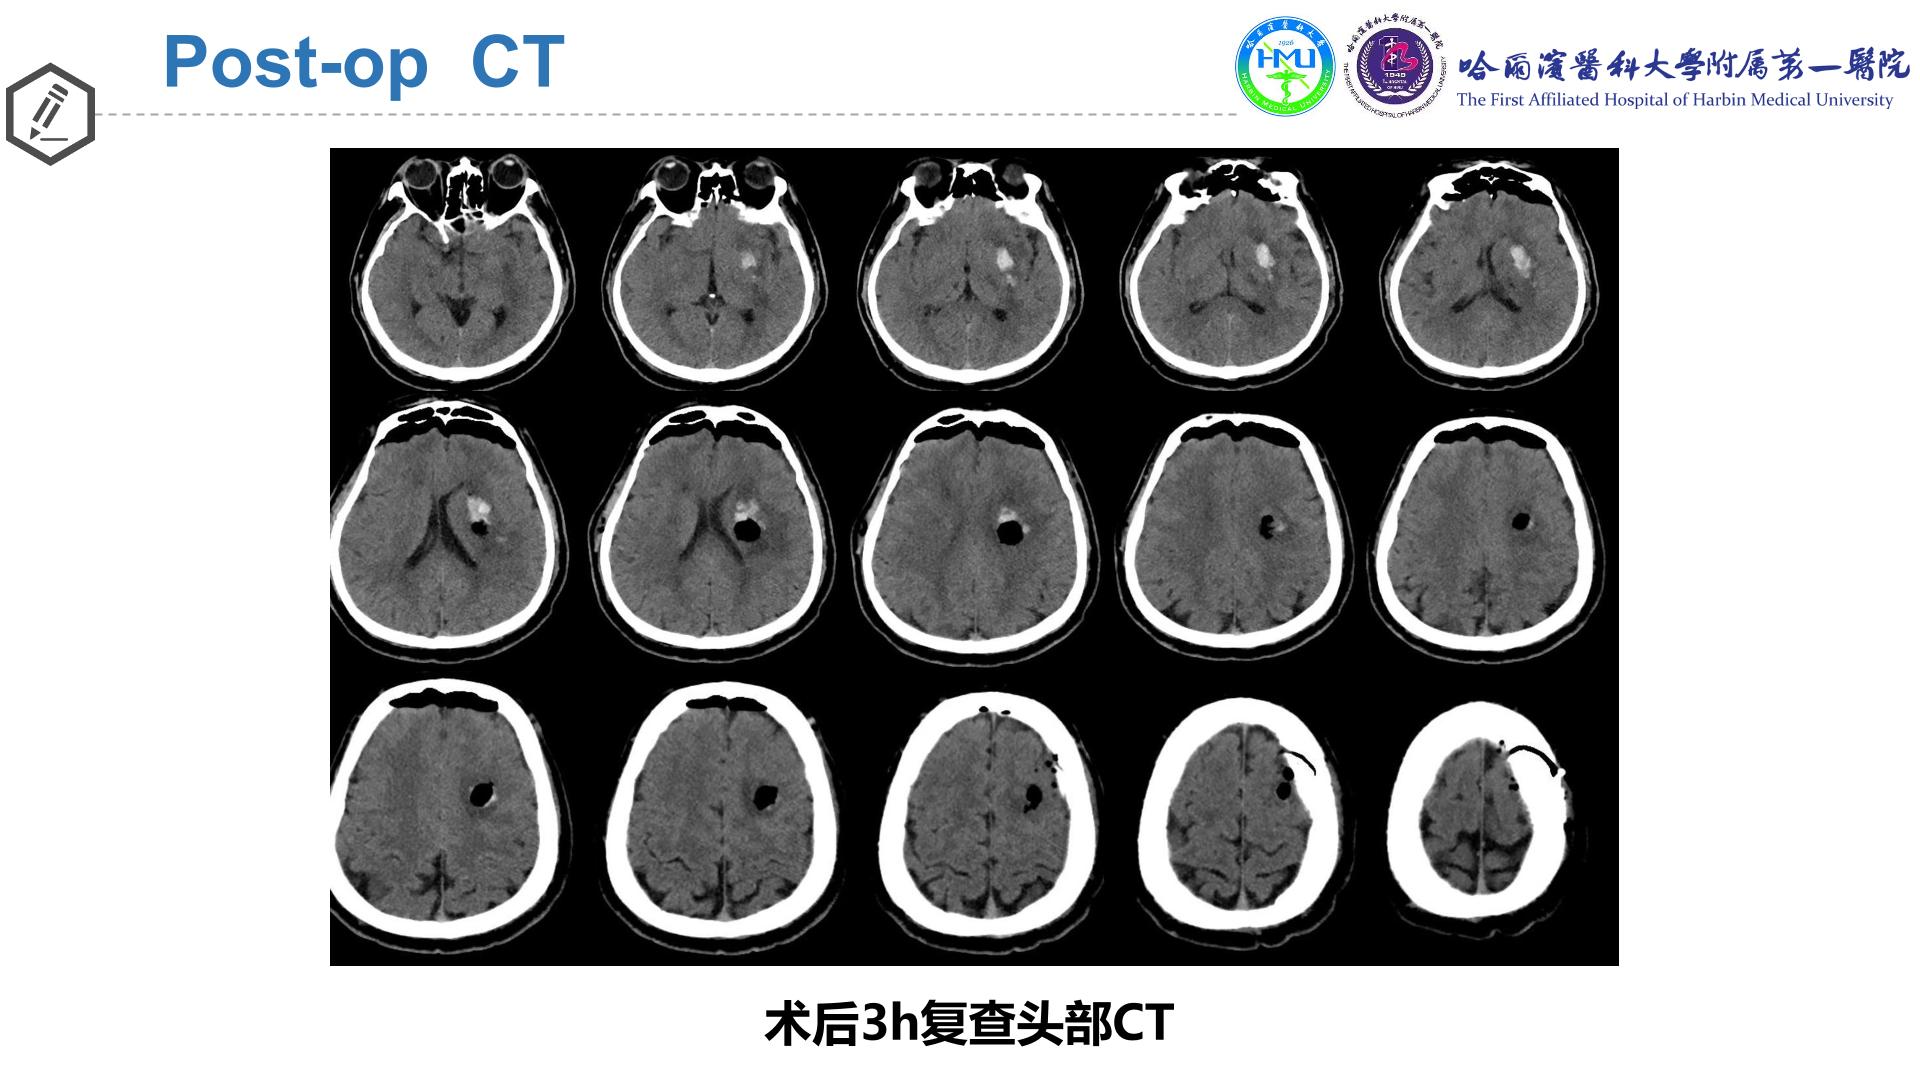

神经导航辅助内镜下清除左侧基底节区脑出血

术后14d

完全性混合性失语→不完全性运动性失语

右下肢肌力0→III级